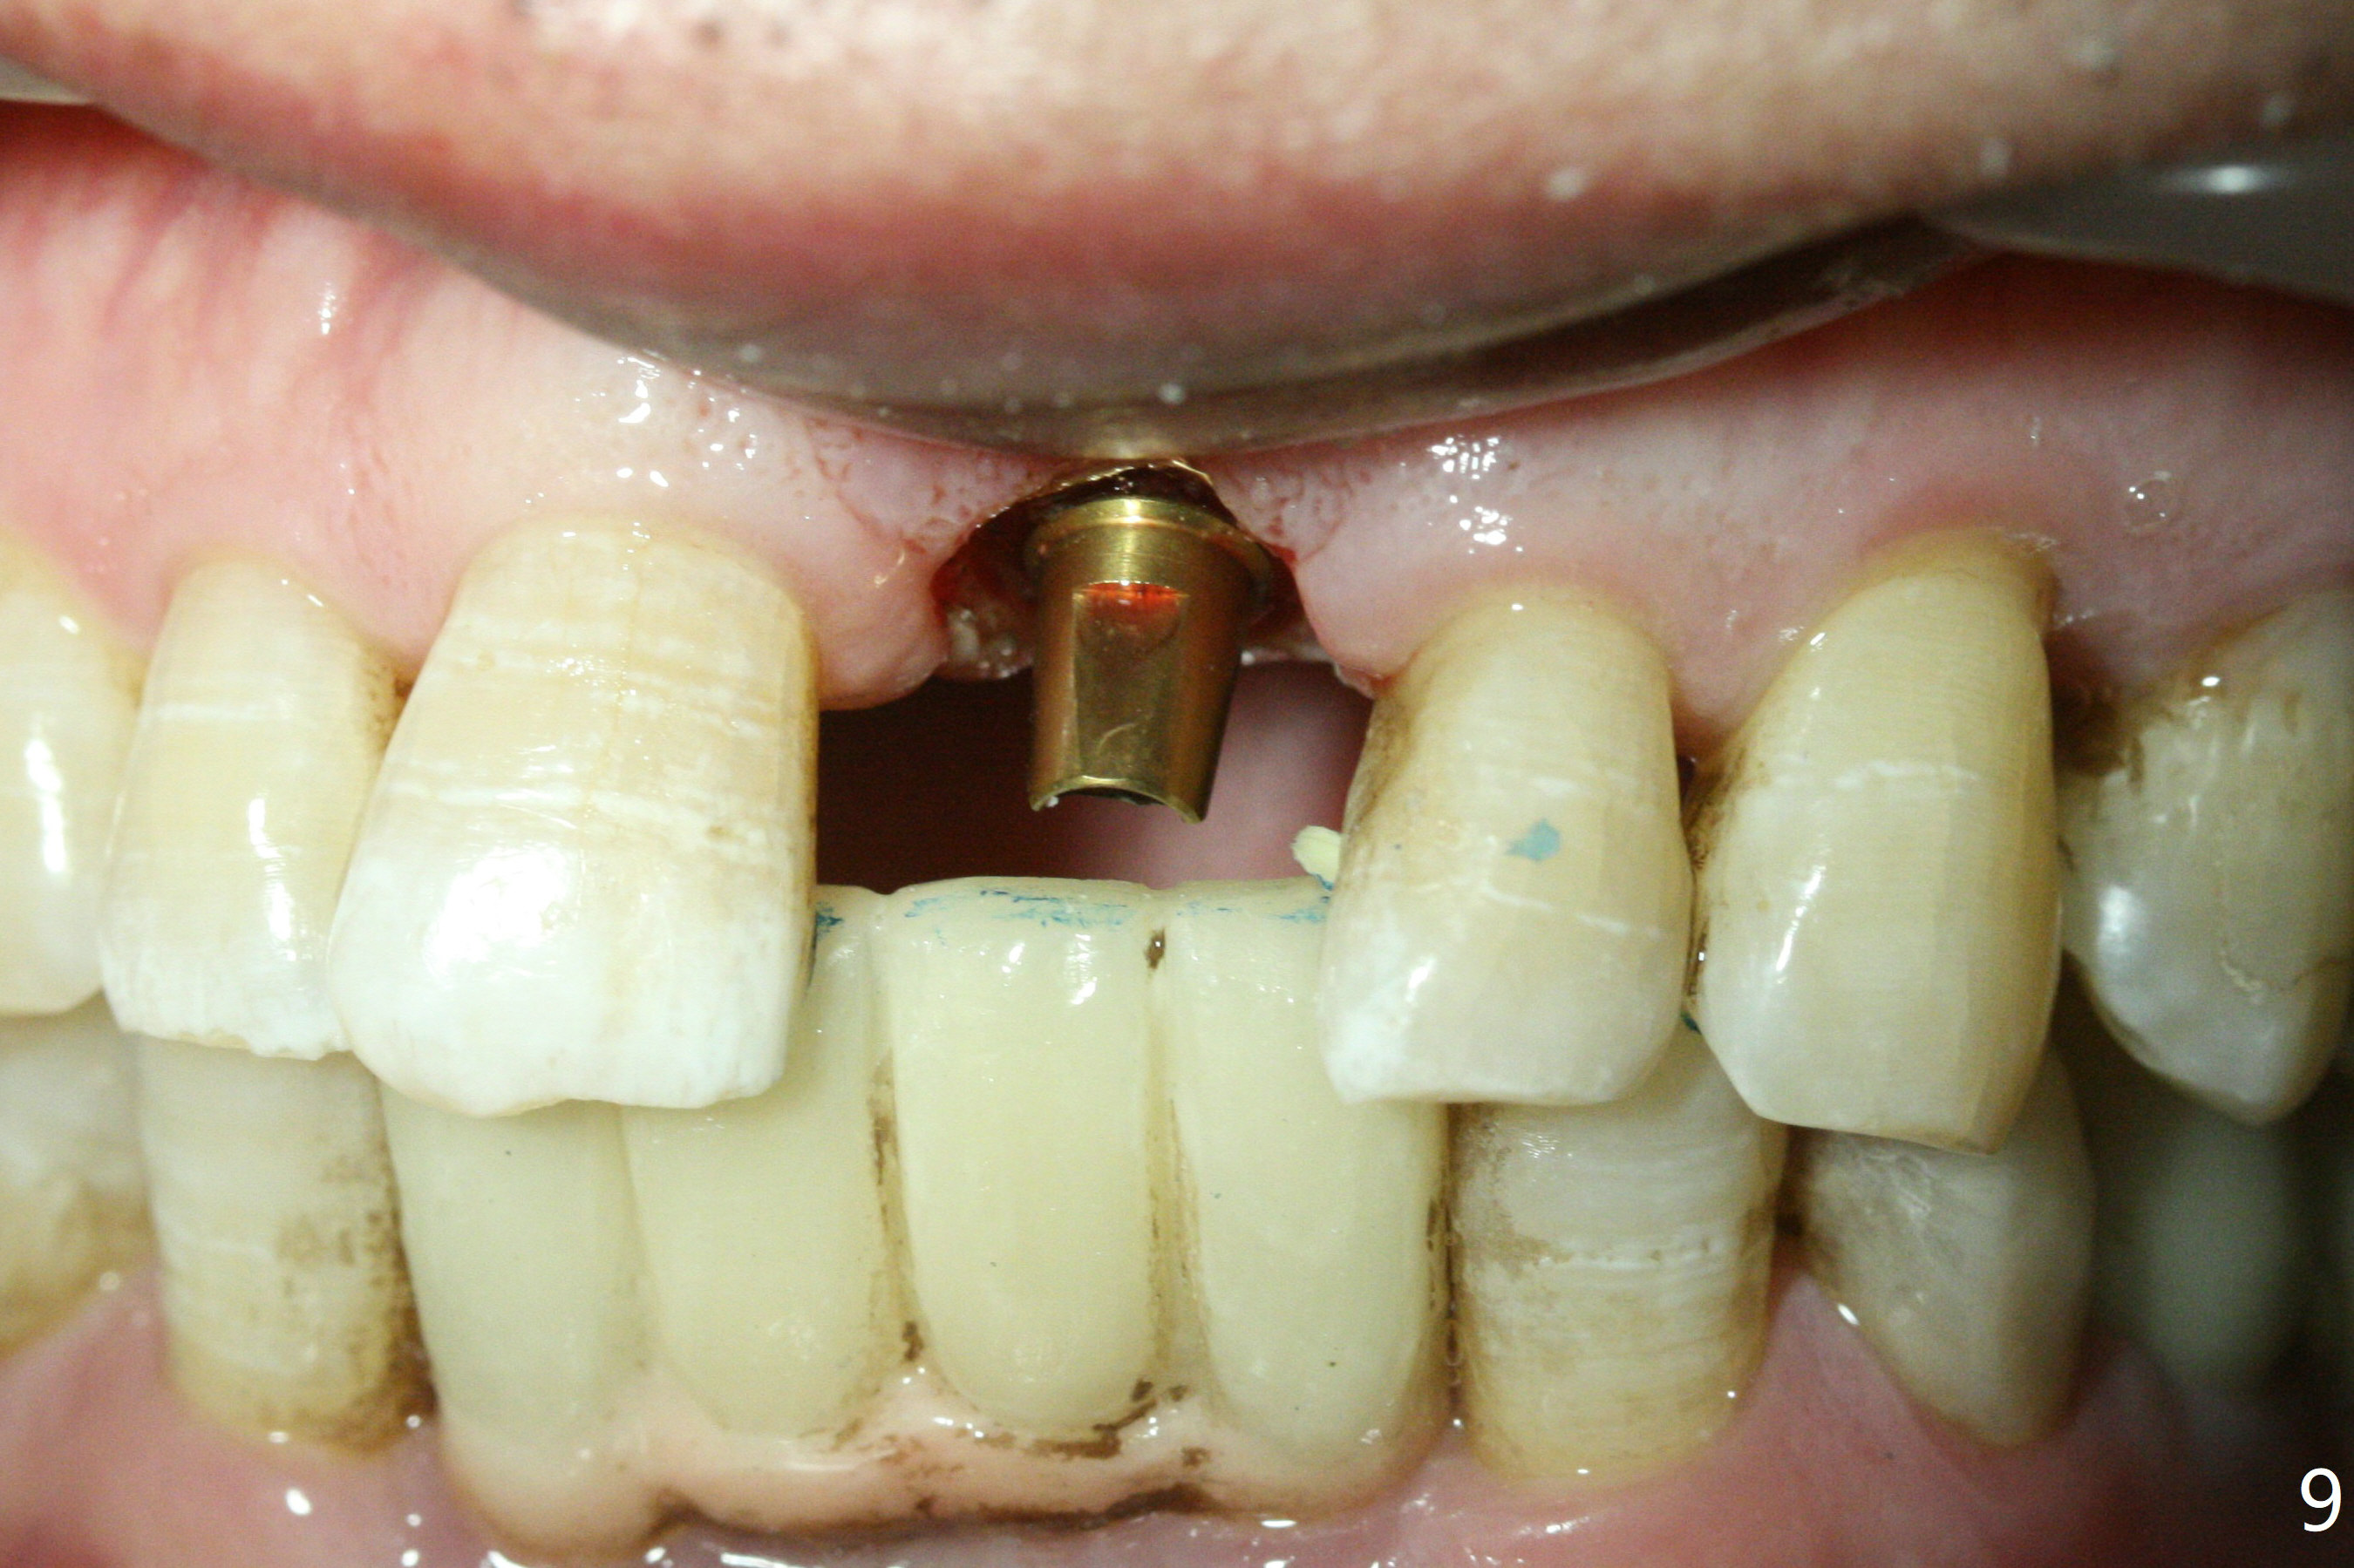

Preop examination shows mobility I of the teeth #8 and 10 and apparent occlusal trauma from #22-26 implant bridge. After occlusal equilibrium, incision reveals low, but moderate ridge at #9 (Fig.1). Fig.2a is a cross section of a normal upper incisor socket with thin buccal plate (B) and thick palatal one (P). It is difficult to initiate osteotomy in the oblique palatal wall when the buccal plate is resorbed (Fig.2b). In this case with horizontal buccal and palatal plate bone loss, the socket bottom is flat (Fig.2c), easy for osteotomy (Fig.2d green arrow, Fig.3). The initial osteotomy deviates mesial (Fig.3). To avoid perforation into the Incisive Canal, the trajectory is changed (Fig.4). After use of the final drill (3 mm), the coronal Incisive Canal is perforated. Following placement of a 3.5x13 mm implant and 4.5x5.5(4) mm abutment, Vanilla Graft is placed (Fig.5 *) to repair the perforation. Retrospectively, the coronal end of the Incisive Canal is revealed at incision (Fig.1 *). The initial osteotomy should be slightly more distal (Fig.3 black line). The buccal plate looks bulky due to placement of the abutment and bone graft 1 week postop (Fig.6,7 (crown dislodgement)). The bone graft appears to remain in place 2 months postop (Fig.8). Impression is taken because of instability of the immediate provisional (Fig.9 after Laser gingivectomy). The gingiva and buccal plate remain healthy 4.5 months postop (Fig.10). A permanent crown is cemented (Fig.11).